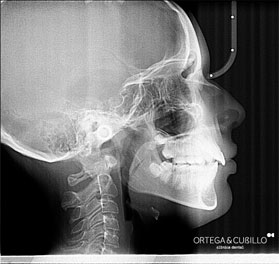

Realizamos ortopantomografías y telerradiografías que son pruebas radiológicas de gran importancia en el tratamiento de ortodoncia e implantología. Asimismo se pueden realizar pequeñas tomografías, radiología de la articulación temporomandibular , senos maxilares y muñeca en este caso para determinar el estado de maduración ósea durante el crecimiento.